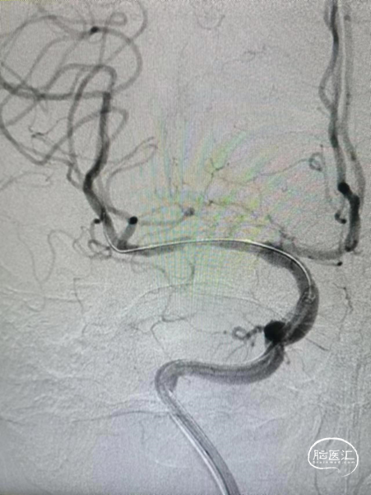

球囊扩张过程。

扩张后造影。